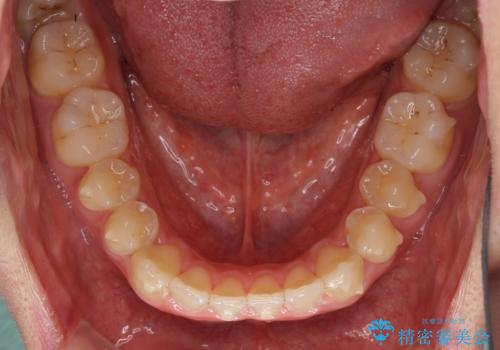

- 上下前歯のデコボコを気にして来院された患者様です。

叢生は軽微であり、費用を抑えて期間もあまりかけずに治療をしたいとのことで、インビザライン・ライトを用いて矯正治療を行うこととしました。

途中通院できなくなり、マウスピースの装着もしっかりとできなかったため、治療期間が長くかかってしまいました。